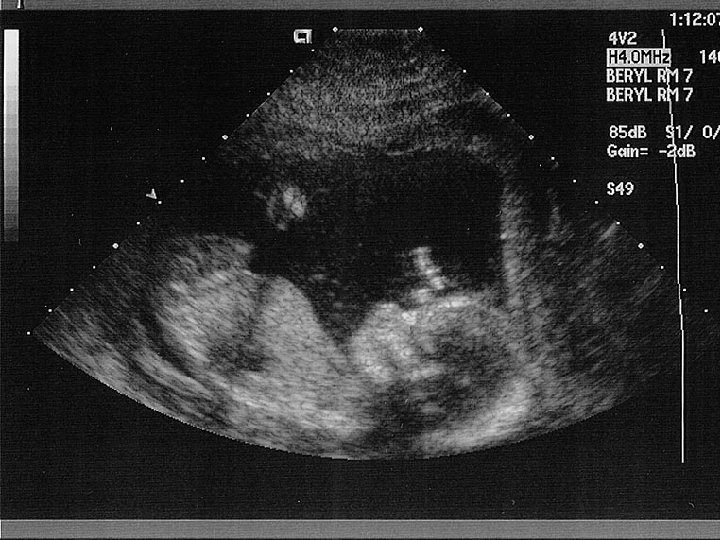

Ultrasound is the region of sound above 20, 000 Hz – it can’t be heard by humans. There a number of uses for ultrasound: 1) Pre-natal scanning 2) Echo sounding

How does ultrasound work? Ultrasonic waves are partly _____ at the boundary as they pass from one _______ to another. The time taken for these reflections can be used to measure the _______ of the reflecting surface and this information is used to build up a _____ of the object. Words – depth, reflected, picture, medium